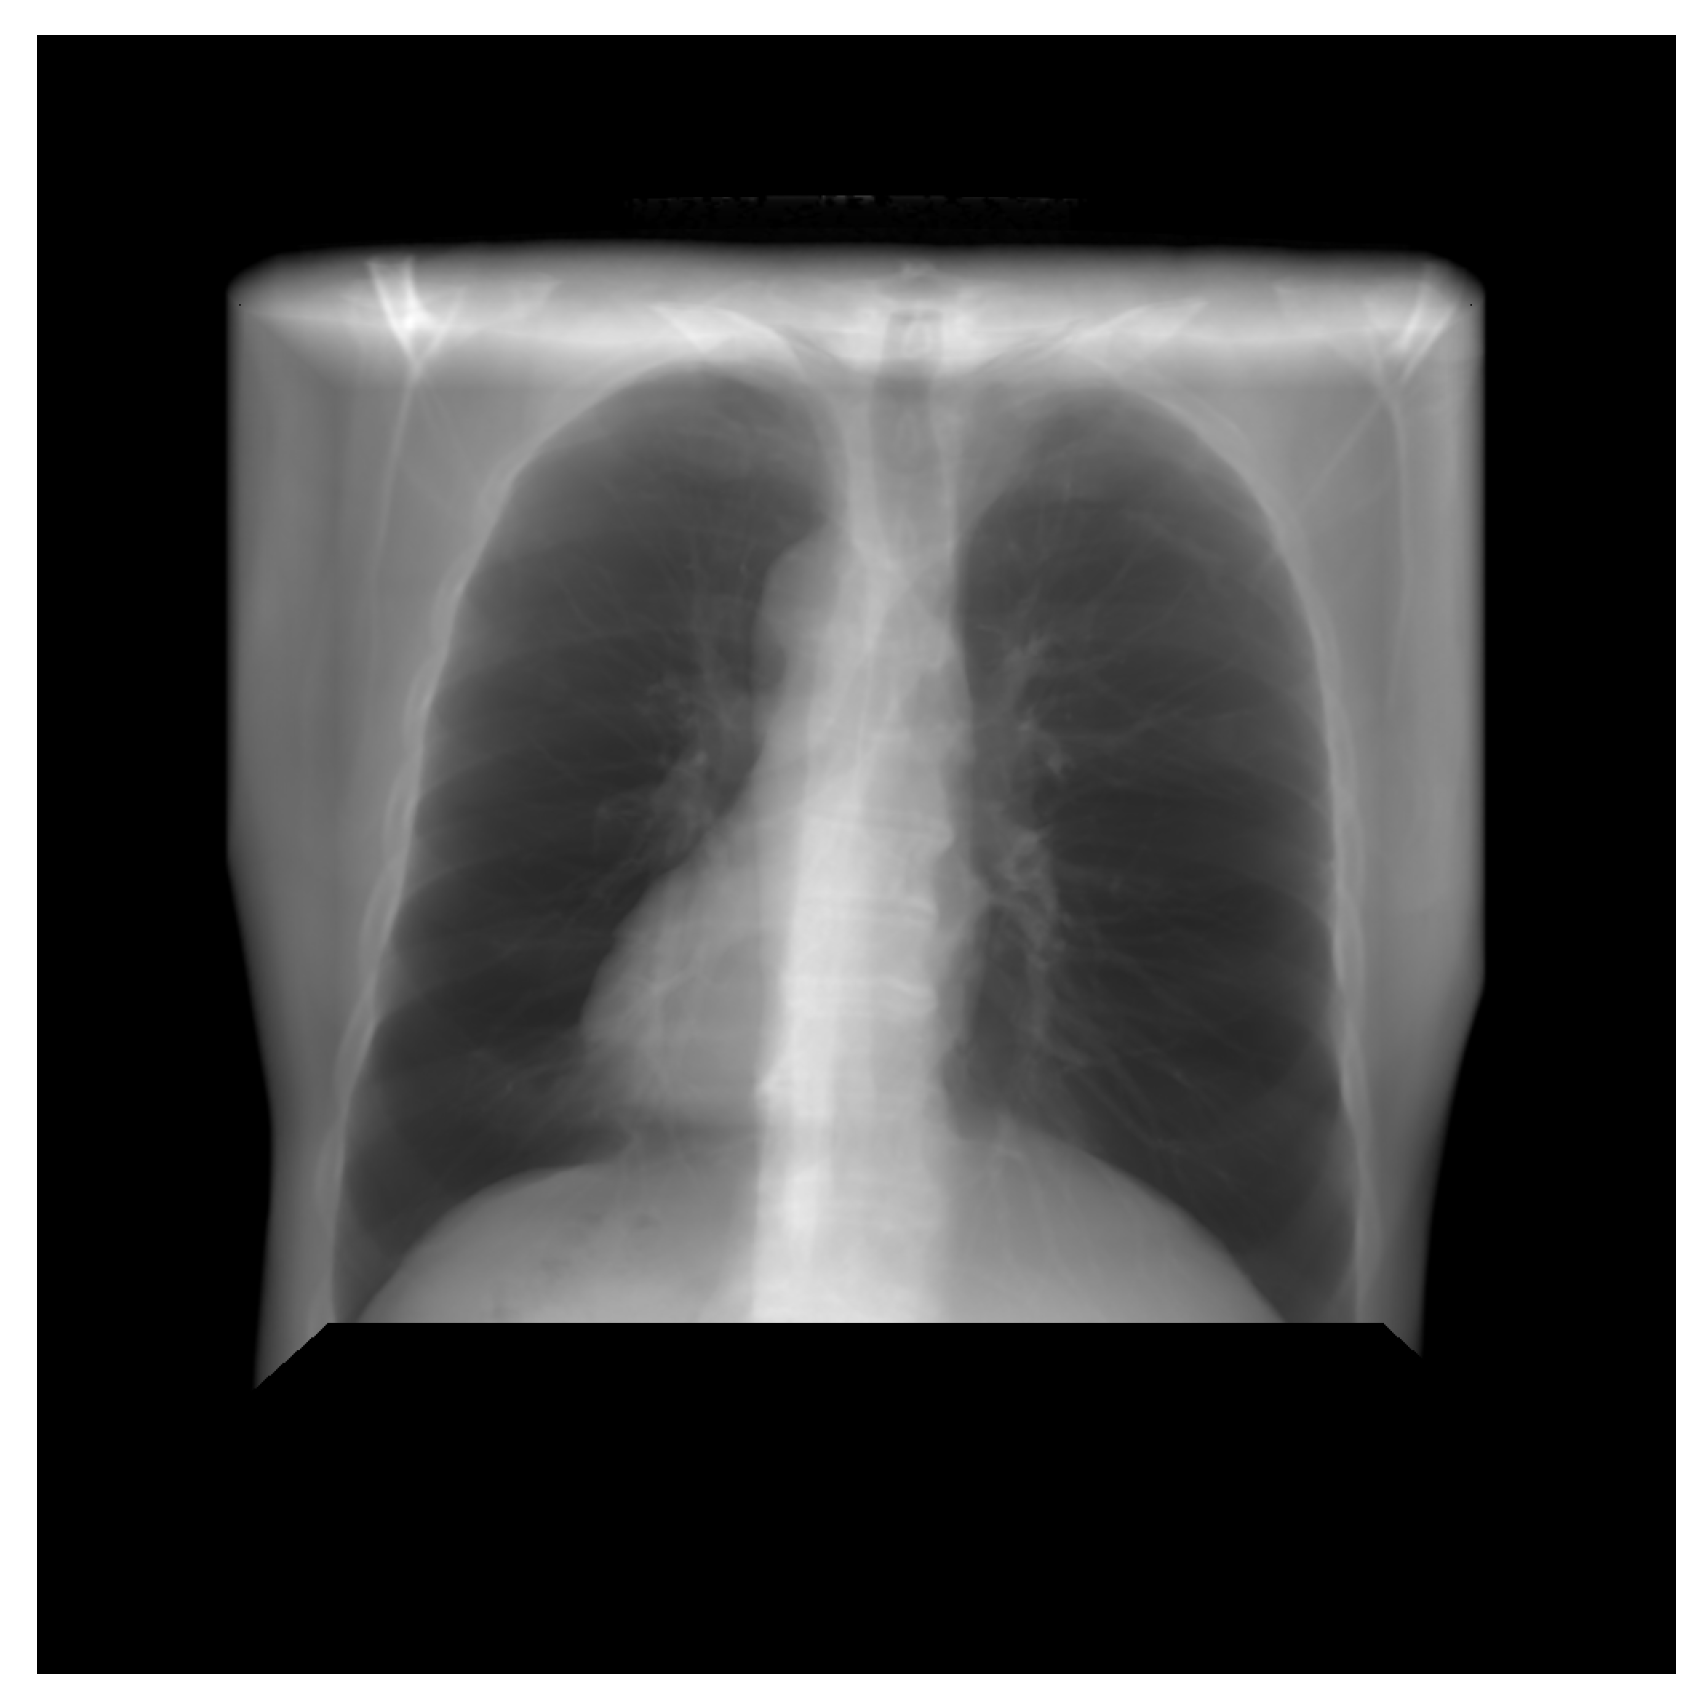

Data utilized in this research were collected from various secondary sources. The chest radiograph was collected from the Department of Health and Human Services, Montgomery County, MD, USA [27]. This dataset consists of 138 frontal chest X-ray images, out of which 80 are normal cases and 58 are cases with manifestations of TB. Moreover, the images are in Portable Network Graphics (PNG) format as 12-bit gray-level images, and the size of each X-ray image is either 4020 × 4892 or 4892 × 4020 pixels. The sample image, along with its GT segmented image from the chest radiograph dataset, is shown in Figure 2 and Figure 3. Further, 23 CT images with segmented CT from VESSELS12 Challenge and 42 CT images with segmented CT from LUNA16 Challenge were downloaded to form a CT dataset. Then X-ray images (DRR) were simulated from CT images. This simulation generated both posterior-anterior (P-A) chest radiographs and lateral chest radiographs. Besides, the lung volume ground truth is available in this dataset, which includes lung statistics such as lung area and lung volumes. Table 1 shows the data used in our study with data source and type. In this research, the number of training samples is small, so data augmentation is performed by rotating, flipping, and scaling the intensity.

Figure 3.

Ground truth segmented image of CXR.